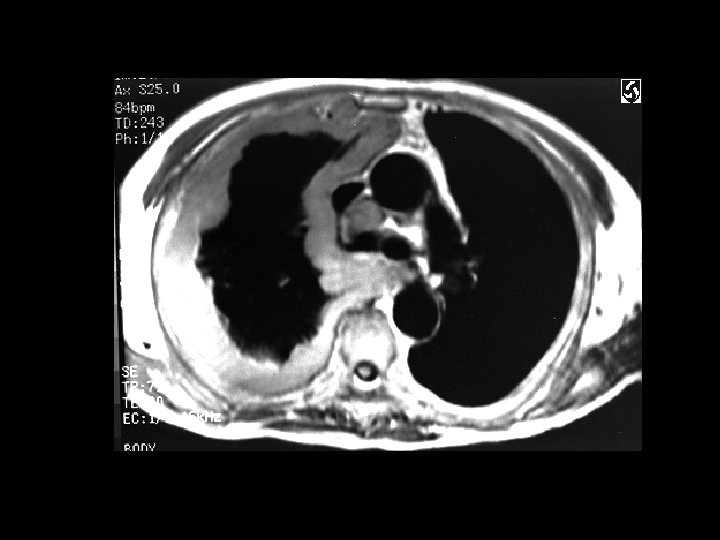

Lymphangioleiomyamatosis (LAM) • Findings: – hyperinflation with a reticular-nodular pattern – multiple thin-walled cysts • Rare dx of young women • present w/SOB, ptx, and chylous effusion • progressively fatal • ddx: – eosinophilic granuloma